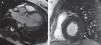

Ante la presencia de un soplo a la auscultación, y la persistencia de fiebre, se realizó un ecocardiograma que demostró una válvula aórtica bicúspide con una imagen de vegetación en el borde libre de sus 2 velos, condicionando una insuficiencia severa. Aunque el origen infeccioso de dicha lesión era improbable debido al resultado negativo de los hemocultivos, se realizó una RMN cardiaca con contraste para esclarecer el diagnóstico. En dicha exploración, además de la vegetación, se apreciaba una imagen de realce subepicárdico a nivel inferolateral, sugestiva de proceso vasculítico (fig. 1), sin evidencia de abscesos, derrame pericárdico ni otras complicaciones.

RMN cardiaca con contraste. A) Secuencia Fast Imaging Employing Steady State Acquisition (FIESTA) en plano de tracto de salida del ventrículo izquierdo (VI), que muestra imagen de vegetación a nivel de la válvula aórtica (flecha). B) Secuencia de realce tardío de gadolinio en eje corto del VI, que demuestra a nivel del segmento inferolateral una imagen de realce subepicárdico sugestivo de proceso vasculítico (flecha).